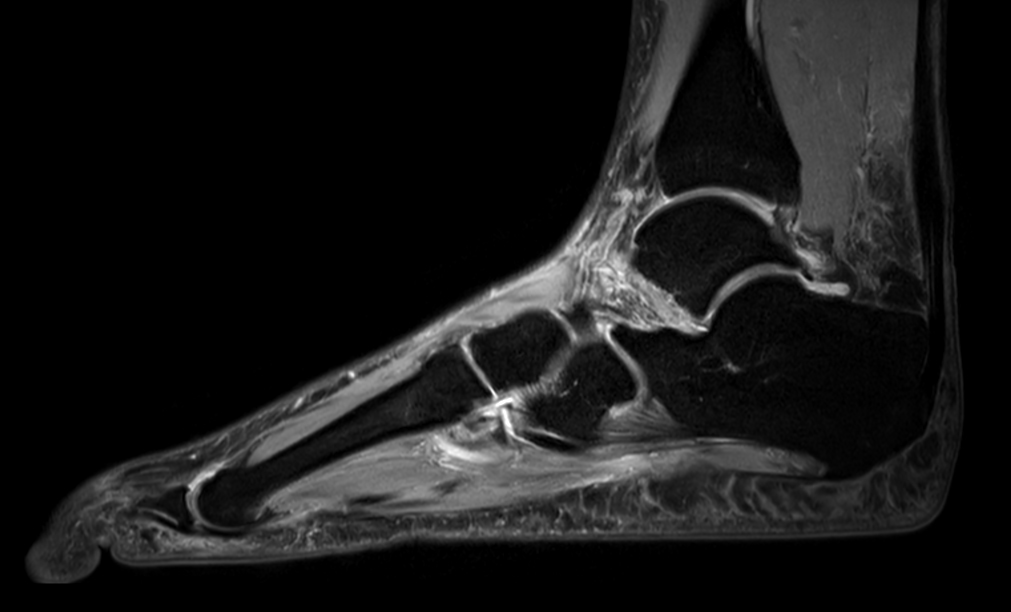

Imaging with the dS 16ch FootAnkle coil

General Hospital Sint Blasius, Dendermonde, Belgium

Patient who was referred for imaging of the achilles tendon